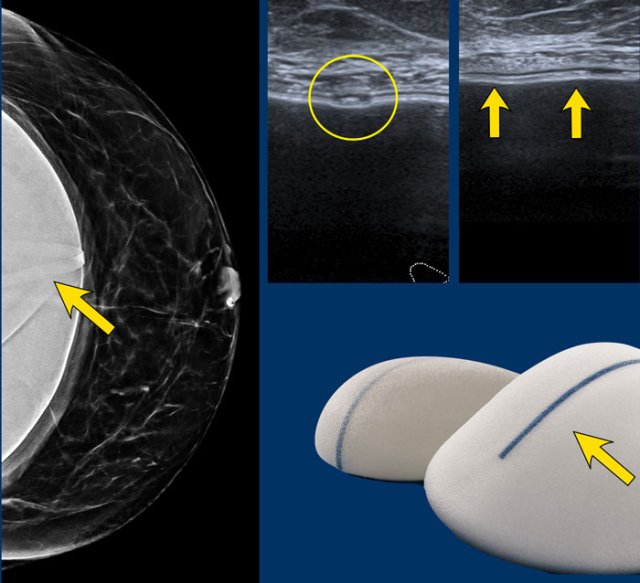

Markings

Mammography showing a breast implant with a small circular band.

On ultrasound it is recognized as a linear structure by looking in two planes (circle on axial scan and arrows on sagittal scan).

It should not be confused with a problem of the envelope.